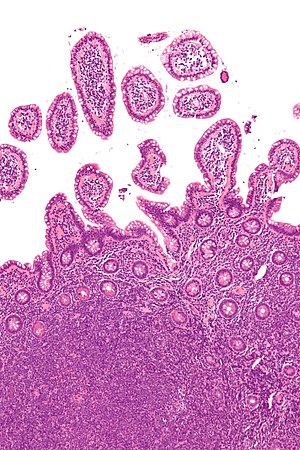

Mantle cell lymphoma - intermed mag.jpg

Micrograph of mantle cell lymphoma, a type of non-Hodgkin lymphoma. Terminal ileum. H&E stain.